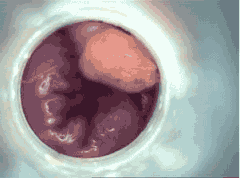

在切除前,必须先查明息肉的具体位置和个数。洛阳东大肛肠医院自2006年引进了电子肛门镜,该设备前端有1200万像素的高清医用摄像头,能清晰观察到病灶,让医患清晰、准确、直观地了解病情,帮助患者选择治疗方案,避免因传统人为检查带来不足而造成病情延误。